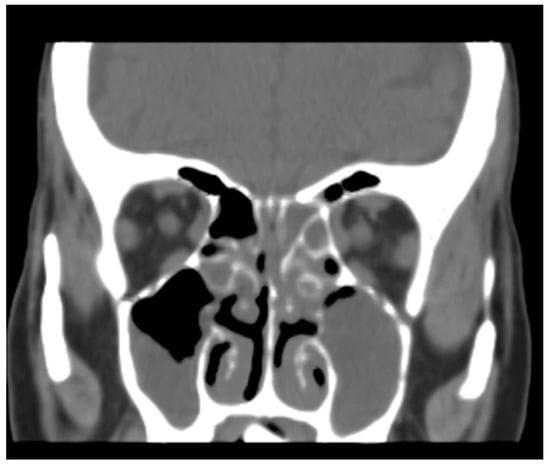

2. Case Report